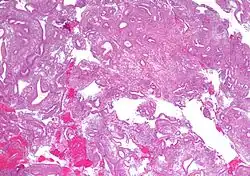

- Atypical endometrial hyperplasia (simple or complex) - Simple or complex architectural changes, with worrisome (atypical) changes in gland cells, including cell stratification, tufting, loss of nuclear polarity, enlarged nuclei, and an increase in mitotic activity. These changes are similar to those seen in true cancer cells, but atypical hyperplasia does not show invasion into the connective tissues, the defining characteristic of cancer. The previously mentioned study found that 22% of patients with atypical hyperplasia eventually developed cancer.[7]

Diagnosis of endometrial hyperplasia can be made by endometrial biopsy, which is done in the office setting or through curettage of the uterine cavity to obtain endometrial tissue for histopathologic analysis. A workup for endometrial disease may be prompted by abnormal uterine bleeding, or the presence of atypical glandular cells on a pap smear.[8]